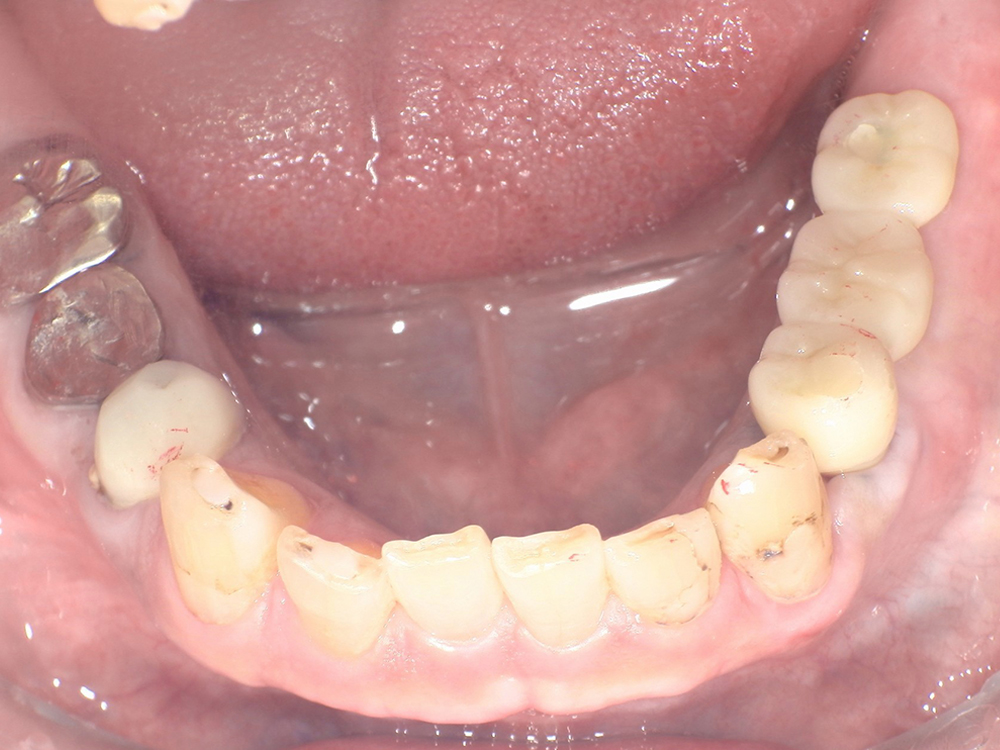

-

<治療前>

<治療後>

主訴:上の前歯を他院で抜かれてしまった。入れ歯は入れたくない。

処置内容:上顎 ストローマンインプラント5本埋入

骨造成:有

静脈鎮静:なし

上部構造:フルジルコニア

費用:¥2,200,000(税込)

治療期間:2カ月

副作用・リスク:

手術後に微熱、腫脹、痣等が生じることがありますが時間と共に消失します。